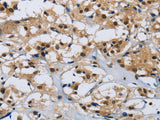

Applications IHC

IHC 1:50-1:200